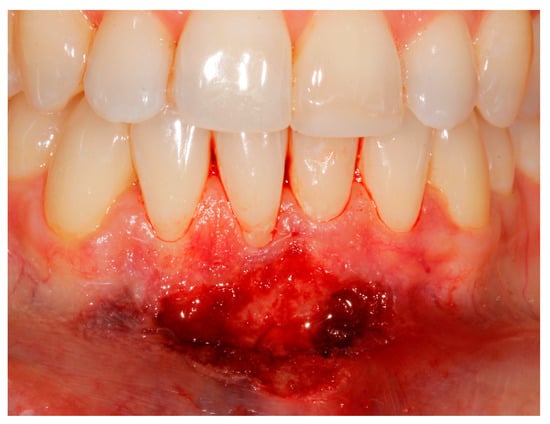

- (a)

- deep partial thickness incision (blade parallel to the periosteum) made at the level of the external insertion of the frenulum;

- (b)

- elimination of superficial mucous tissue and muscle of the frenulum;

- (c)

- a series of detached points with periosteal anchorage for the apical positioning of the lining mucosa of the lip and the second intention healing of the exposed periosteum.